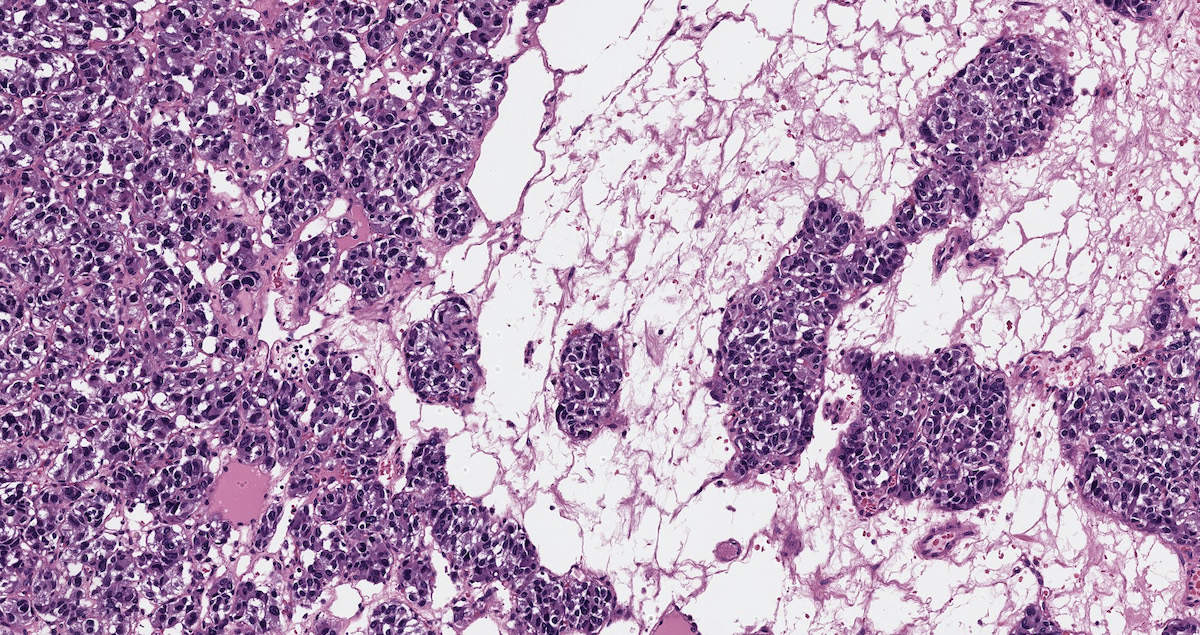

Microscopic (histologic) description

- Prevailing histologic pattern: epithelioid chief cells arranged in distinctive clusters / nests (zellballen pattern), separated by prominent fibrovascular stroma (J Clin Med 2018;7:280)

- Trabecular pattern: ribbons or cords of epithelioid cells divided by fibrous bands

- Other patterns: pseudorosette, angioma-like, spindled and sclerosing

- Chief cells: round, oval to polygonal cells with abundant granular basophilic, eosinophilic or amphophilic cytoplasm (Surg Pathol Clin 2019;12:951)

- Intracytoplasmic hyaline globules may be present in sympathoadrenal paragangliomas

- Giant multinucleated cells and bizarre cells can be present (Srp Arh Celok Lek 2002;130:7)

- Scattered ganglion cells can be seen

- May have dysmorphic vessels, melanin-like pigment (neuromelanin) (pigmented paraganglioma), amyloid, abundant stroma and osseous metaplasia (Diagn Pathol 2012;7:77, Hum Pathol 1992;23:33)

- Necrosis is unusual except in patients who have undergone preoperative tumor embolization

- Special histopathologic features usually related to genetic syndromes:

- VHL syndrome: prominent stromal edema, clear cytoplasm and lipid degeneration (Am J Surg Pathol 1987;11:480)

- SDHx related syndrome: granular eosinophilic cytoplasm (Am J Surg Pathol 2020;44:422)

Microscopic (histologic) images

Contributed by Luvy Delfin, M.D. and Sylvia L. Asa, M.D., Ph.D.